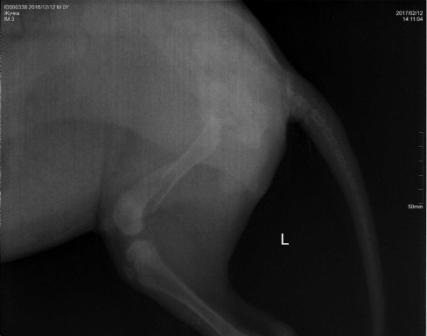

12.02.2017г. к воротам подкинули коробку с щенком (сука). У щенка перелом обеих задних лап. Правая - перелом в области коленной чашечки, левая лапа - перелом в области бедренной кости и коленной чашечки. Ей необходима операция! Стоимость операции 10500р. Необходимую сумму нужно собрать в течении недели, щенок не может ходить и жить полноценной жизнью...

Прием щенка осуществлял специалист хирург-ортопед из Москвы (Ветеринарный центр МЕДВЕТ). Оперировать будем в ЛПВЦ ПеСиКоТ г. Петушки, здесь же и делали рентген. Телефон для связи: 8-919-021-43-91 Мария